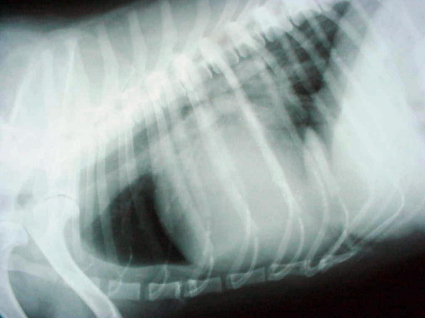

Desafío Veterinario: Soplo mitral sistólico grado IV/VI

Cocker Spaniel Inglés dorado de 11 años con problemas de higiene oral y síntomas cardíacos, incluyendo soplo mitral, tos seca y fatiga. Diagnóstico de insuficiencia cardiaca congestiva. Tratamiento inicial con ramiprilo y espironolactona no exitoso, síntomas empeoran. Frecuencia respiratoria de 45 rpm, frecuencia cardiaca de 200 lpm. Evaluación continua recomendada."